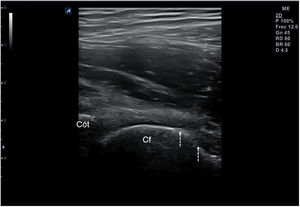

Técnica de exploraciónLa exploración ecográfica se realiza con sonda lineal de alta frecuencia (7,5-12MHz). Se debe hacer de forma estandarizada en las distintas áreas anatómicas, que permita identificar los diferentes tejidos, tanto normales como patológicos, observados en reposo y en movimiento. Los signos ecográficos patológicos habituales son la colección hipo- o anecoica comprimible y desplazable en recesos articulares en los derrames (fig. 10), el engrosamiento hipo- o anecoico del tejido en una vaina sinovial con o sin líquido en la tenosinovitis (fig. 11), la interrupción y espiculación de la línea cortical en las erosiones óseas (fig. 12), la aparición de material ecogénico en el espacio sinovial o articular en las sinovitis y el pannus respectivamente, y la presencia de señal doppler en los procesos con inflamación activa (fig. 13). Deben identificarse en 2 planos distintos para evitar la confusión por la presencia habitual de artefactos. Se ha de aplicar gel suficiente que permita el contacto de toda la superficie de la sonda con la piel, evitando el aire entre ambos, y se debe ejercer una presión firme pero no excesiva, que impida colapsar los neovasos visibles mediante el doppler. Estos serán más fáciles de encontrar con la articulación en flexoextensión fisiológica.